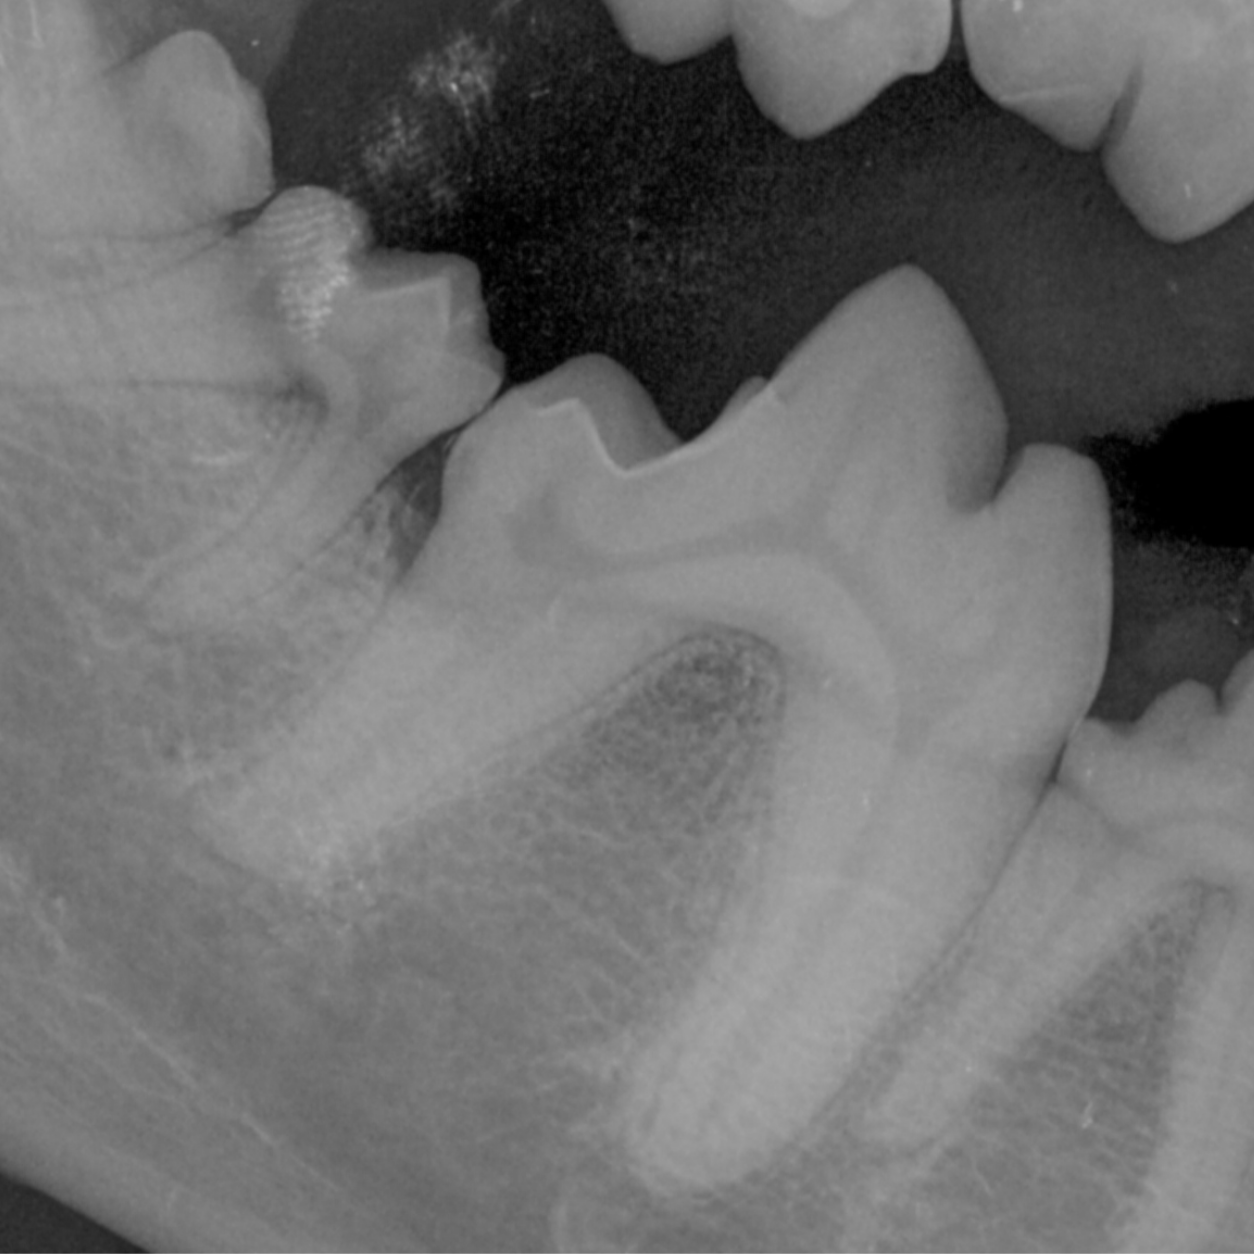

Veterinary dental radiographs are performed to assist in diagnosing any existing dental diseases. Veterinary professionals take dental radiographs to be able to administer the proper care needed.

Dental radiographs are highly recommended during a dental cleaning to reveal any diseases a pet may encounter. A pet should also be brought in for a dental radiograph if they are experiencing any discomfort in their mouth. Signs of discomfort can include: eating irregularly, finicky eater, and/or loss of appetite.